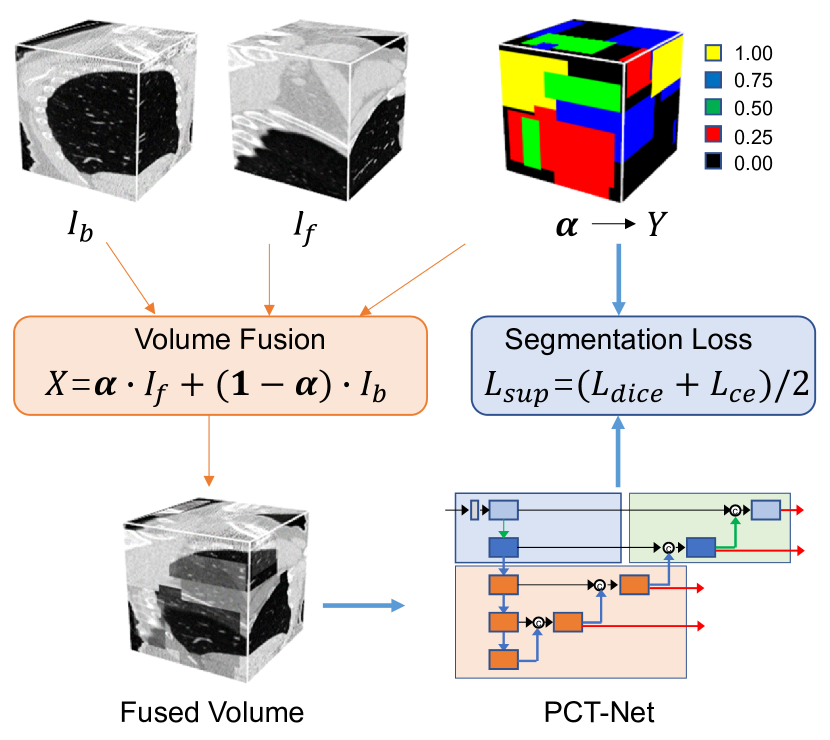

To address these issues, we propose a novel self-supervised pretraining strategy named Volume Fusion (VF) for 3D medical image segmentation. Differently from existing SSL methods that define pretext tasks as image-level classification or image restoration, our method uses a pseudo-segmentation pretext task that pretrains a 3D segmentation model directly. Specifically, it fuses a foreground sub-volume from a 3D image with a background sub-volume from another image based on a fusion coefficient map, and the coefficient of each voxel takes values from a discrete set where each element is treated as a class. The model to pretrain takes the fused sub-volume as input, and predicts the class label of each voxel, which is exactly a supervised segmentation pretext task, as illustrated in Fig. 1. It has several advantages over existing pretraining approaches for medical image segmentation models. First, compared with existing supervised learning-based pretraining [24, 20], it generates paired input images and segmentation label maps automatically, which does not require manual annotations, making it be able to easily leverage unannotated images at a larger scale for pretraining at zero annotation cost. Second, compared with methods that only pretrain a feature encoder [7, 12, 3], it pretrains the encoder and decoder at the same time, leading the entire segmentation model to be sufficiently pretrained. In addition, compared with image restoration [52, 16, 10], the gap between pretraining and downstream tasks are minimized, as both of them are formulated as segmentation tasks, which makes the features learned during pretraining be more transferable to downstream segmentation.

Fig. 1 shows an overview of our proposed method for pretraining with unannotated 3D medical images. We introduce a pretext task based on pseudo-segmentation, where Volume Fusion (VF) is proposed to generate paired images and segmentation labels to pretrain the 3D segmentation model, which can better match the downstream task of segmentation than existing SSL methods. The pretraining strategy is combined with our proposed PCT-Net to obtain a pretrained model that is applied to segmentation of different objects from 3D medical images after fine tuning with a small set of labeled data.

The main idea of Volume Fusion-based SSL is to fuse two sub-volumes with discrete voxel-level coefficients (i.e., different fusion categories), and train a model taking the fused sub-volume as input to predict the fusion category of each voxel, which is a supervised segmentation pretext task.

3.1.1 Volume Fusion

Let and denote two sub-volumes cropped from two different 3D scans, respectively, and their size is denoted as , where , and are the depth, height and width, respectively. We use as the background sub-volume, and as the foreground sub-volume, and they are fused into a new sub-volume :

| (1) |

where is the fusion coefficient map, and its -th element represent the coefficient for voxel . takes values from a discrete set =, where is the number of non-zero fusion coefficients, and it corresponds to the foreground class number in the fusion output.

To model the pretext task as a segmentation task, we take each element in as a class, leading to classes of fused voxels in . We use to denote the class label map corresponding to , and the -th voxel’s class label is 0, 1, 2, …, for = 0.0, , , …, 1.0, respectively.

3.1.2 Pretext Task based on Segmentation

During the pretraining process, for each pair of and , we generate the fusion coefficient map by setting the fusion coefficient values of different local patches randomly. Specifically, assume the foreground patch number in is , where and are the minimal and maximal possible values of , respectively. We select foreground patches at random sizes sequentially, and set the fusion coefficient in each patch as a random value from {, , …, 1.0}. For voxels outside of these patches (i.e., the background region), the value is set to 0.0. Then the generated is used to fuse and to obtain , and the corresponding label map converted from is used as the segmentation ground truth for . Then a supervised segmentation loss based on Dice loss and cross entropy loss is used to pretrain the segmentation model based on the paired and :

| (2) |

| (3) |

| (4) |

where is the voxel number. is the predicted probability of voxel being class , and is the corresponding one-hot ground truth value obtained from . The pseudo code of SSL based on Volume Fusion is shown in Algorithm 1.